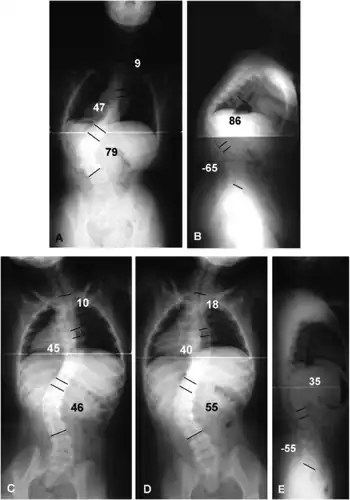

a) Scoliosis of T5-T11 was 47°, that of T11-L3 was 79°, and L3 tilt was 34°. b) kyphosis of T7-L1 was 86°. c,d)in the lateral bending film, the thoracic and thoracolumbar curves were rigid e) the lateral traction film, kyphosis was improved to 35° (T7-L1)